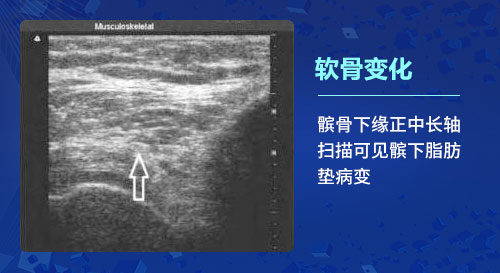

一、軟骨變化:骨關(guān)節(jié)炎的基本病理改變是軟骨變性,出現(xiàn)軟骨細(xì)胞纖維化、骨質(zhì)增生及滑膜炎等改變。肌骨超聲檢查能夠發(fā)現(xiàn)骨關(guān)節(jié)炎患者初始的軟骨改變,在軟骨的厚度基本上沒(méi)有發(fā)生實(shí)質(zhì)性變化的時(shí)候就可以發(fā)現(xiàn)軟骨透聲模糊、邊緣毛糙等細(xì)微的變化;利用高分辨率能力,檢查軟骨完整性(毛糙、變鈍、分布不均)及厚度、軟骨透聲的清晰程度以及軟骨表面的輪廓光滑度的變化,甚至出現(xiàn)局限性變薄或消失,以此很好的反映骨關(guān)節(jié)炎各個(gè)階段的病理變化。